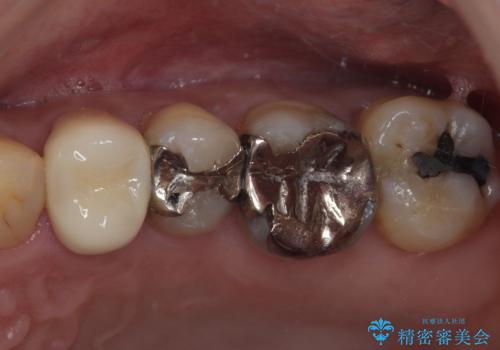

銀歯を外したい オールセラミッククラウン

担当医 有澤哲郎